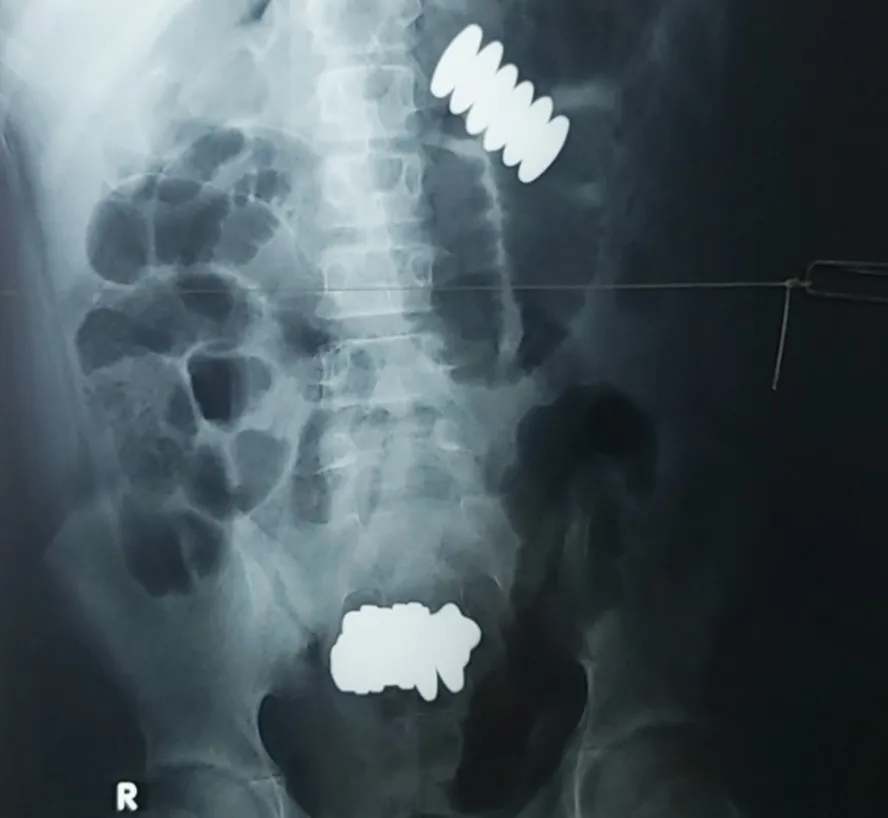

Các BS chỉ định chụp X quang phát hiện có hai khối dị vật bên trong cơ thể bé trai. Cụ thể, quai ruột chứa nhiều khối nam châm, thành ruột viêm, thủng nhiều lỗ, bờ nham nhở.

![]() |

Hình chụp X quang phát hiện có hai khối dị vật bên trong. Ảnh: BVCC |